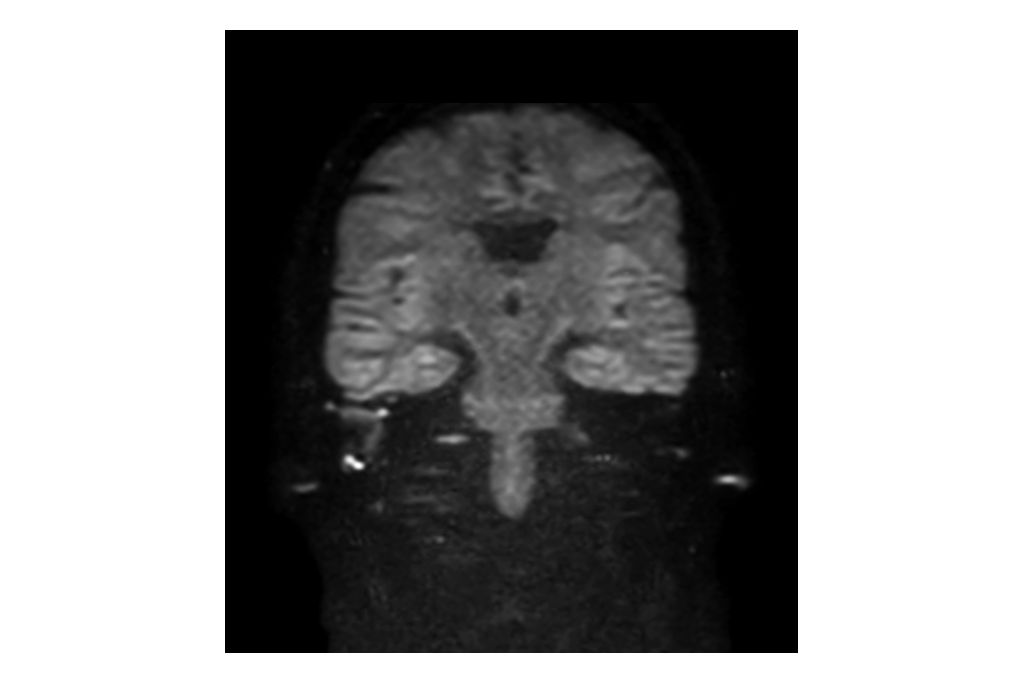

Philips - DWI TSE - Brain MR Clinical application